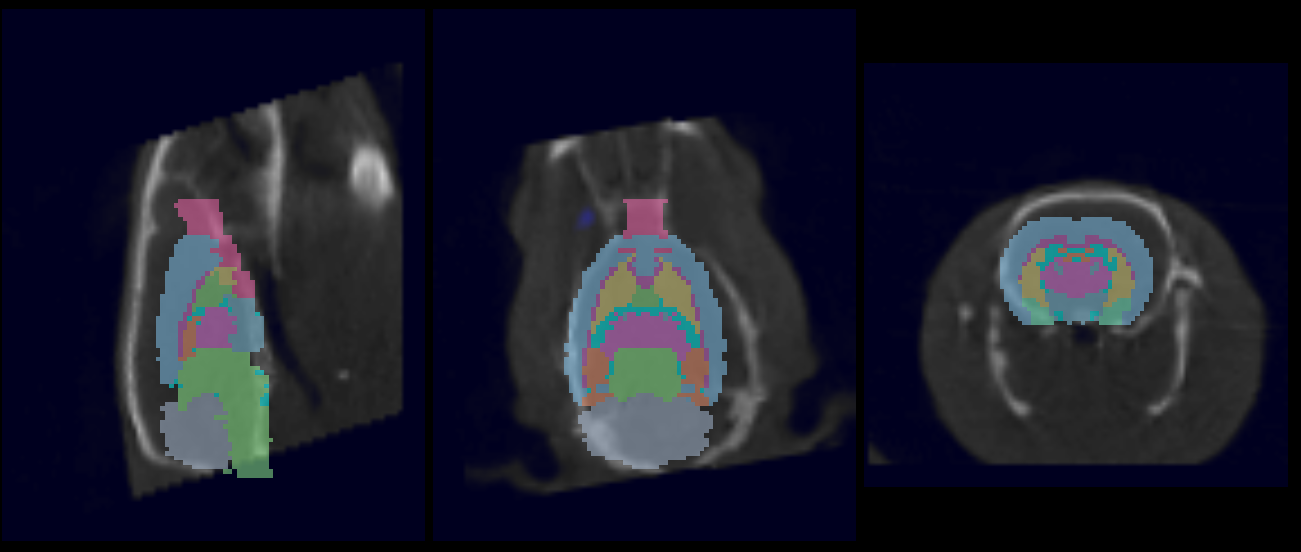

The 3D Brain Atlas Analysis Tool is designed for automatic segmentation of brain image data. Automated fusion routines register an application-specific brain atlas to pre-clinical image data (or vice versa) and advanced statistical analysis methods are employed to provide rapid and thorough region-specific volume and uptake quantification.

Use the 3D Brain Atlas Tool to perform brain region analysis. The tool can handle CT or MR data as the input and MR, PET, or SPECT for the input functional data.